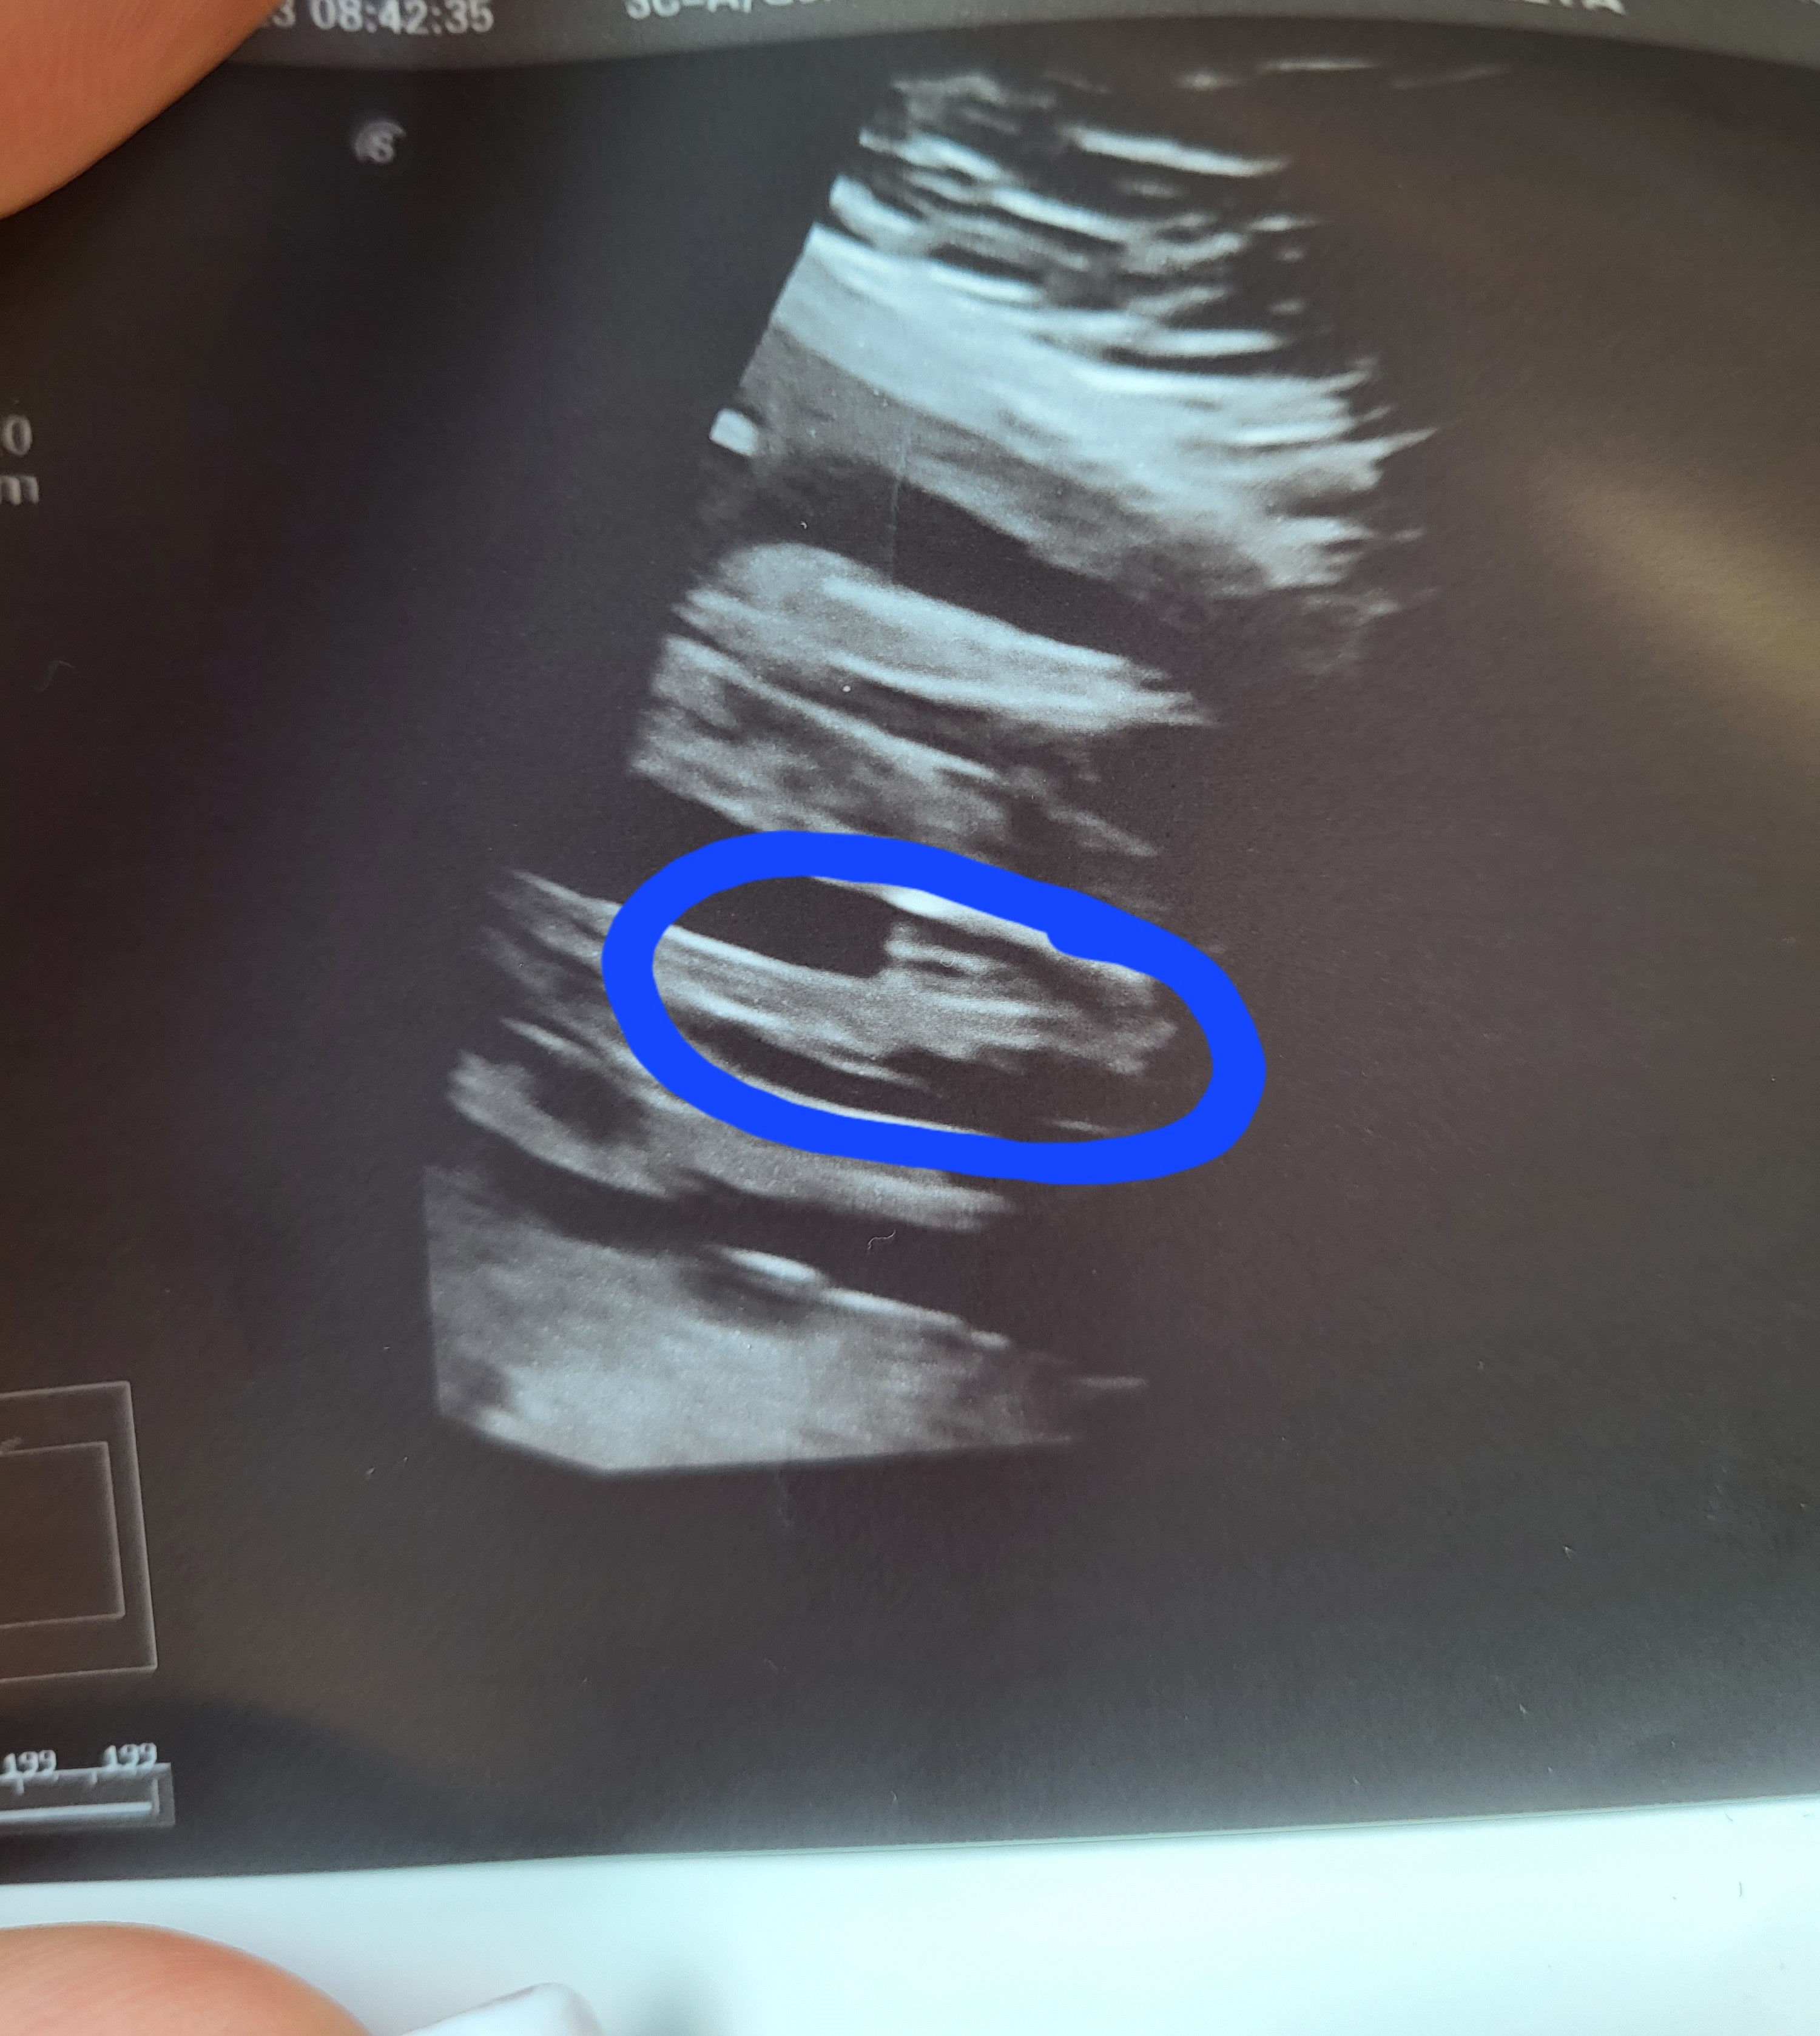

Cześć dziewczyny. Od początku ciąży zarówno lekarz z prenatalnych jak i mój lekarz mowią ze bedzie dziewczynka. Na 2 prenatalnych lekarz powiedział ze dziecko zle ułożone ale wydaje mu się ze chlopczyk. Teraz 26 tydzień. Moja lekarka mowi bez wątpliwości, że widzi wargi sromowe. Za 2 tyg mam 3 prenatalne ale ciekawość mnie zżera. Co myślicie o tym? Czy to faktycznie mogą być wargi? :) położna twierdzi ze na zdjęciu z prenatalnych to bardziej pepowina niż siusiak.